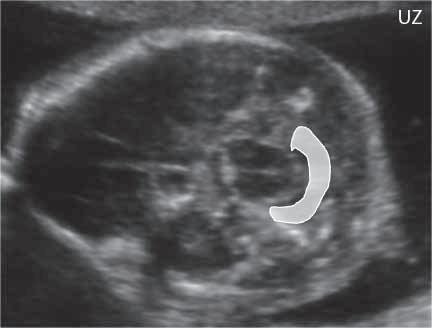

Obr. I.1.7g Šipky ukazují příznak citronu – vkleslé části lebky frontálně, Chiariho malformace, prenatální UZ (snímek zapůjčen z archivu prof MUDr P Caldy, CSc )

Obr. I.1.7h Příznak banánu (bíle označen) – mozeček posunut dorzálně, tvoří konvexní strukturu, Chiariho malformace, prenatální UZ (snímek zapůjčen z archivu prof MUDr P Caldy, CSc )